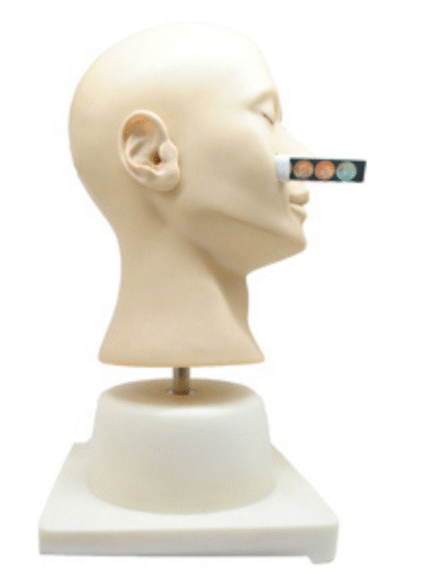

ATL-114 ADVANCED EAR INPECTION SIMULATOR SOFT

ATL-115 ADVANCED EAR IRRIGATION SIMULATOR SOFT

ATL-116 ADVANCED EAR DIAGONOSTIC SIMULATOR SOFT

ATL-119 LOCAL ANESTHESIA TRAINING KIT SOFT